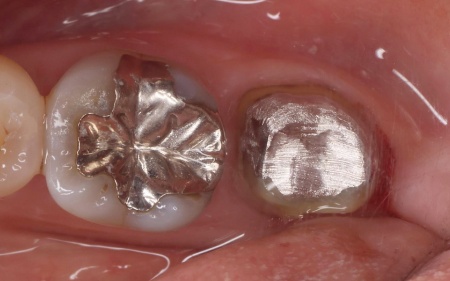

60代女性 炎症を起こした奥歯に根管治療を行いジルコニアクラウンで修復した症例

「噛むと違和感があり、痛みもある」とご相談いただきました。

レントゲン撮影をして詳しく拝見したところ、左下奥歯に慢性歯根膜炎が認められました。

慢性歯根膜炎とは、歯の神経が通っている根管から歯根を覆う歯根膜が細菌感染して、炎症が起きる病気です。

このまま放置すると細菌感染がさらに進行し、歯根周囲の骨が破壊されて最終的には歯を失うおそれがあるため、早急に治療をする必要があると診断しました。

患者様は「この機会に完治させたい」と希望されたため、根管治療を施したあと、歯全体をすっぽりと覆う被せ物で噛み合わせを回復する治療方法を提案しました。

まずは左下奥歯に根管治療を行い、MTAセメントを用いて根の先端まで隙間なく封鎖します。